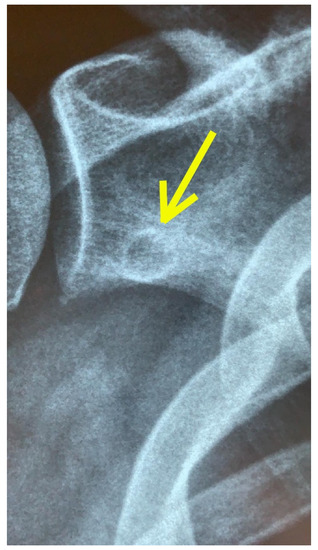

3.2. Imaging